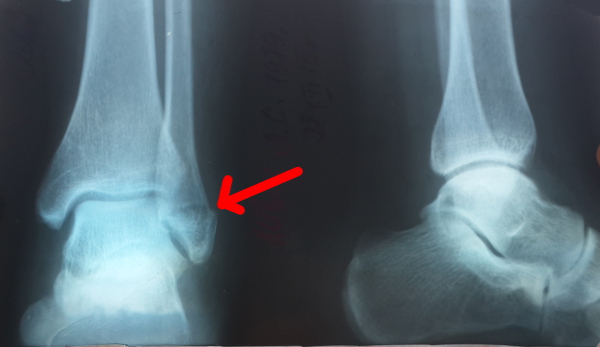

Диагностика

Как правило, постановка предварительного диагноза возможна после осмотра и опроса пациента. Между тем, дополнительно врач рекомендует пройти рентгенографию в трех проекциях:

- прямой – выполняется в положении лежа на спине с ногой, согнутой в колене;

- косой – лежа на здоровом боку с ногами, согнутыми в коленях, между которыми укладывается подушка;

- боковой – лежа на больном боку с согнутыми в коленях конечностями, когда поврежденная укладывается впереди.

Рентгенография также выполняется на всех этапах лечения и реабилитации для контроля их качества.